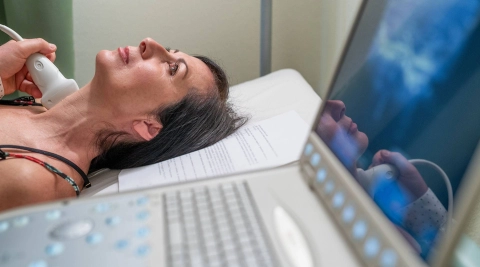

Schulterschmerzen zählen zu den häufigsten Gelenkbeschwerden – die Ursache ist jedoch nicht immer leicht zu erkennen. Belastende Armbewegungen sollten dann vermieden werden.

Mehr erfahren

Bei einer Schultersteife beginnt die Schulter, allmählich ohne erkennbaren Grund zu schmerzen und steif zu werden. In der Regel heilt eine Schultersteife von allein wieder aus.

Mehr erfahren